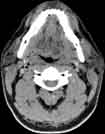

Visible Human male: Sectio transversalis 1200

CT

NMR

Pd T1 T2